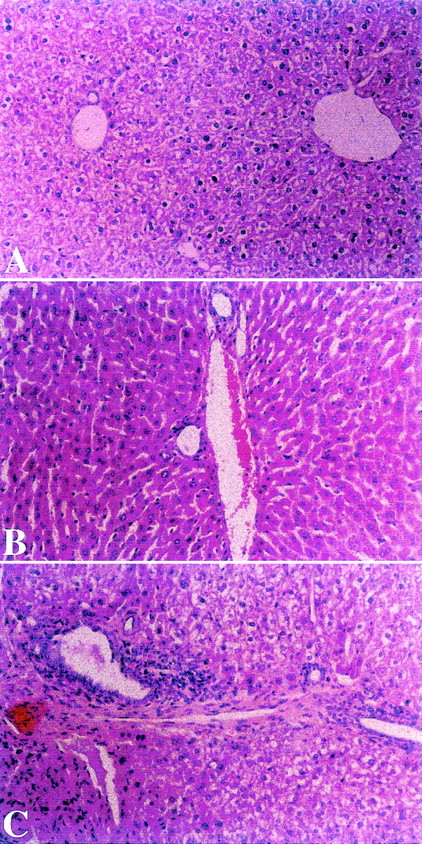

Amelioration of cGVHD associated-liver disease by oral tolerance.

Liver biopsies were performed on all splenocyte recipients from all groups 52 days after transplantation. Mice in experimental group A, fed after transplantation with homogenates of splenocytes derived from recipient strain BALB/c mice, showed mild degrees of portal inflammation, lymphocyte infiltration, and/or disruption of intrahepatic bile ducts (Figure 3A). In contrast, biopsy specimens from control nontolerant recipients in groups B and C, fed after transplantation with homogenates prepared from B10.D2 mouse splenocytes or BSA, respectively, showed portal inflammation and bile duct destruction (Figure 3B and C). With the use of the standardized score grading for liver and bile duct involvement in cGVHD, group A recipients achieved a sum score of 1.90 ± 0.42, compared with 2.3 ± 0.41 and 2.58 ± 0.38 in control groups B and C (n = 6, group A vs B, P < .005; group A vs C,P < .004).

Liver biopsies were performed on splenocyte recipients 52 days after transplantation. Mice in experimental group A, fed after transplantation with homogenates of splenocytes derived from recipient strain BALB/c mice showed mild degree of portal inflammation (Panel A). In contrast, biopsies from control nontolerant recipients in groups B and C, fed after transplantation with homogenates prepared from B10.D2 mouse splenocytes or BSA, respectively, showed portal and bile duct inflammation (Panels B and C). (HαE, original magnification ×40.)

Effect of toleration on histologic evaluation of liver in transplants recipients.